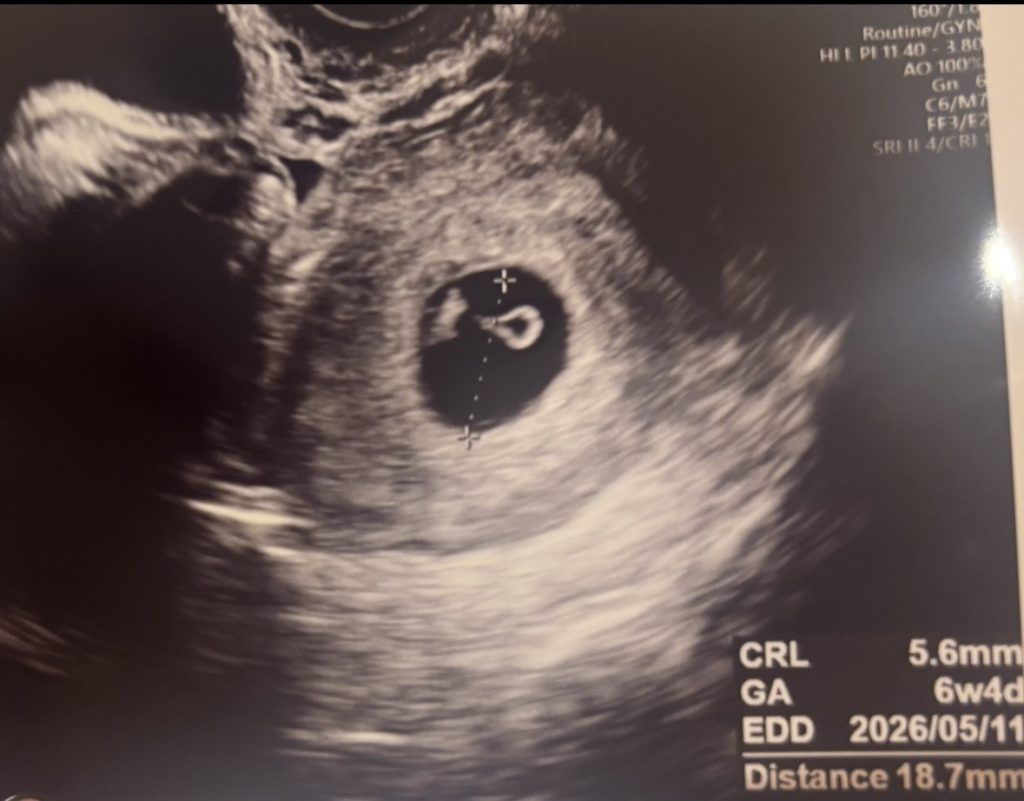

エコー写真(妊娠7週0日)

Screenshot

7週0日、前回とエコーの様子がまた変わっていました。

前回の卵黄嚢に加えて、赤ちゃんの体(胎芽)も確認できます。

心拍が聞こえたことと、赤ちゃんをエコーで確認出来たことで、前回よりも妊娠した実感が湧いてきました

エコー写真右下の数値の意味はこんな感じ。

CRL・・・頭の先からお尻までの長さ

Distance・・・胎嚢の大きさ

エコー写真の右下に表示されているCRLとは、頭の先からお尻まで長さです。

CRL5.6mm

1cmにも満たないのにしっかり命が芽生えているんだなと感動しました。

胎嚢の大きさですら18.7mm

2cm弱の小さな袋で妊娠の確認が出来るなんて、医療の技術はすごいなと思いました。

小さい胎芽がピコピコ動くのが、心拍とのことだったのですが、本当にわずかな動きすぎて、赤ちゃんの心臓が動いている、という感覚はまだ分かりませんでした、、(笑)